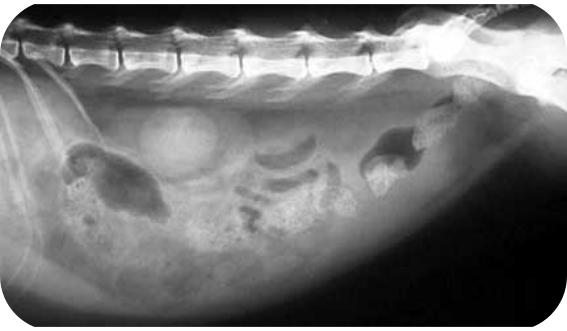

② 腹腔、胸腔和心包积液,腹部肿大,有肿块或呼吸困难;

患病猫咪的腹部X光成像